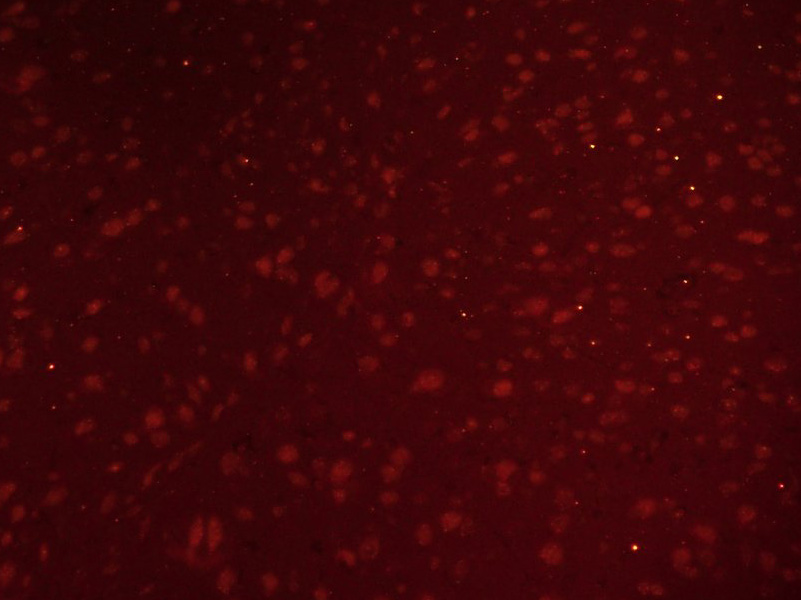

產(chǎn)品圖片

Paraformaldehyde-fixed, paraffin embedded (Mouse brain); Antigen retrieval by boiling in sodium citrate buffer (pH6.0) for 15min; Block endogenous peroxidase by 3% hydrogen peroxide for 20 minutes; Blocking buffer (normal goat serum) at 37°C for 30min; Incubation: Anti-GLI1 Antibody, conjugated (bs-1206R-BF555) at 1:100 overnight at 4°C; DAPI (5ug/ml, blue, C-0033) was used to stain the cell nuclei.